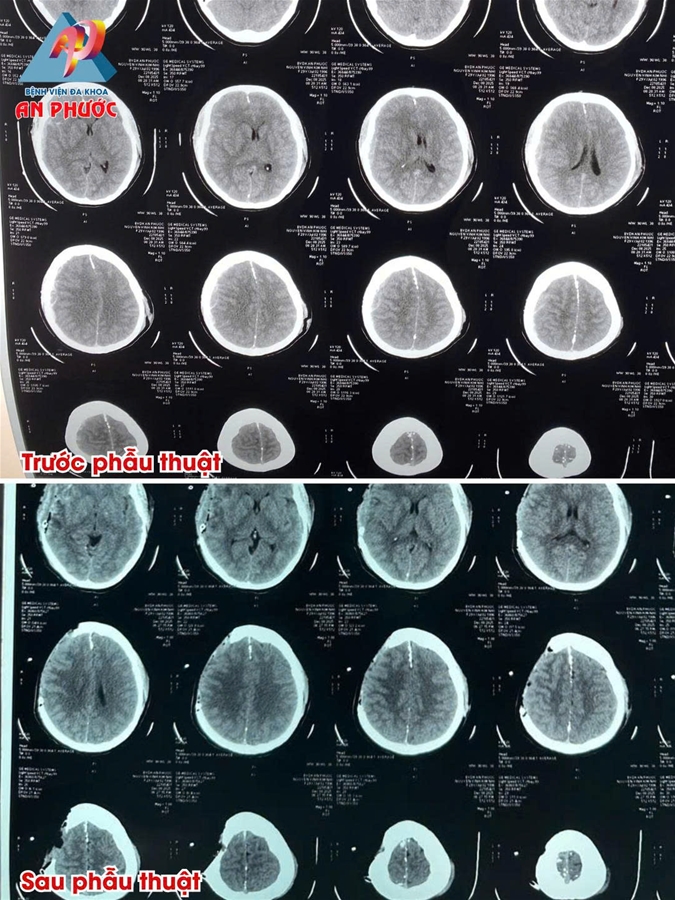

👉 Kết quả chụp Cắt lớp vi tính sọ não ghi nhận: Tụ máu dưới màng cứng bán cầu phải, dập não thùy thái dương phải, xuất huyết dưới nhện, phù não, nứt xương trán đính trái, xương đá trái và thành xoang bướm hai bên. Đây là tổn thương sọ não phức tạp, có nguy cơ đe dọa đến tính mạng nếu không được can thiệp kịp thời.

👉 Sau 03 giờ phẫu thuật, ê-kíp được lấy 45 gram máu tụ dưới màng cứng bán cầu phải và não dập thái dương phải.

👉 Sau 07 ngày điều trị, bệnh nhân tỉnh, sinh hiệu ổn, hiện đang được tiếp tục theo dõi, chăm sóc và điều trị.